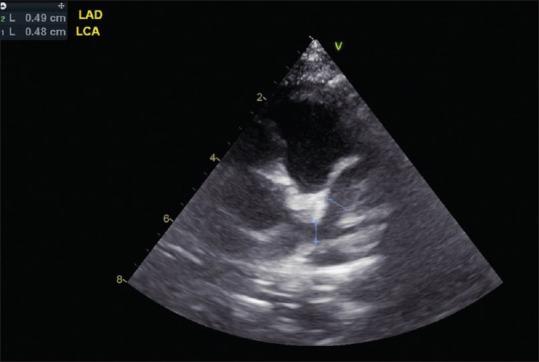

Kawasaki disease (KD) is an etiology-unknown but with a generalized inflammatory disorder of multiple organs and systems in childhood. The basic pathologic changes are panvasculitis of the small and medium-sized arteries, mainly the coronary arteries. It is now the leading cause of acquired heart disease during childhood in developed countries and has led to the early development of angina pectoris, myocardial ischemia/infarction, and even sudden cardiac death in early adulthood. Although there is no definitive diagnostic test for KD, the accurate diagnosis is dependent on the clinical presentations to meet the diagnostic criteria. Echocardiography is a well-known noninvasive tool to detect structural abnormalities and evaluation of cardiovascular function. It has been reported to detect accurately the early and late cardiovascular abnormalities, including perivascular brightness, lack of tapering, dilatation, and aneurysmal formation of coronary arteries as well as the mitral/aortic regurgitation, pericardial effusion, and myocardial functional changes in KD. In cases of incomplete form of KD and patients whose clinical manifestations did not meet the diagnostic criteria, abnormal echocardiographic findings of coronary artery may provide the assistance for early diagnosis of KD. Long-term periodic echocardiographic follow-up is the basic and essential study for patients of KD with initial coronary arterial abnormalities. Ninety nine articles that studied echocardiographic findings of KD had been reviewed and will be discussed.

川崎病(KD)是一种病因不明的儿童期多器官和系统的全身性炎症性疾病。基本病理变化是中小动脉的全血管炎,主要是冠状动脉。它现已成为发达国家儿童后天性心脏病的主要原因,并导致成年早期心绞痛、心肌缺血/梗死,甚至心源性猝死的早期发生。虽然目前尚无针对KD的确切诊断试验,但准确诊断依赖于临床表现符合诊断标准。超声心动图是一种众所周知的用于检测结构异常和评估心血管功能的非侵入性工具。据报道,它能准确检测KD早期和晚期的心血管异常,包括血管周围亮度、缺乏逐渐变细、扩张以及冠状动脉瘤形成,还有二尖瓣/主动脉反流、心包积液和心肌功能变化。在不完全型KD病例以及临床表现不符合诊断标准的患者中,冠状动脉超声心动图异常表现可为KD的早期诊断提供帮助。长期定期的超声心动图随访是初始冠状动脉异常的KD患者的基础且必要的检查。已对99篇研究KD超声心动图表现的文章进行了综述并将予以讨论。